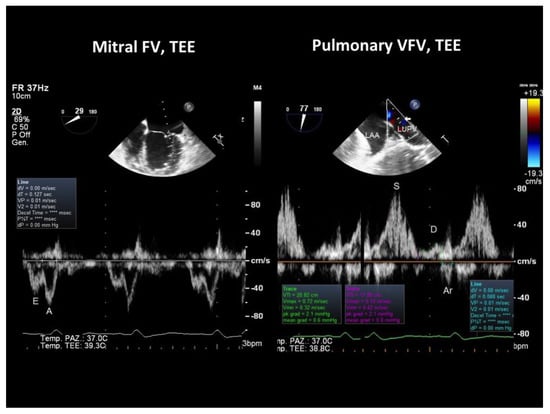

2.2. Assessment

2.3. Echocardiographic Evaluation